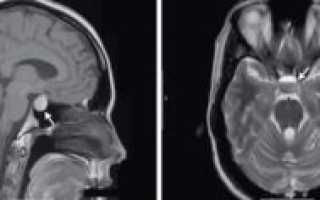

- МРТ головного мозга.

Определить что это синусопатия по МРТ можно благодаря степени изменению слизистой оболочки. Кроме этого магнитно-резонансная томография позволит определить наличие новообразований.

Во время диагностики необходимо сдать общий анализ крови, который поможет определить наличие и количество эозинофилов – основных показателей возникновения синусопатии. Важным этапом является процедура МРТ – магнитно-резонансной томографии.

С помощью МРТ врач может детально осмотреть состояние пазух носа, выявить изменение их слизистой оболочки, появление опухоли и т.д.

Чтобы предотвратить поражение головного мозга, проводится магнитно-резонансная томография.